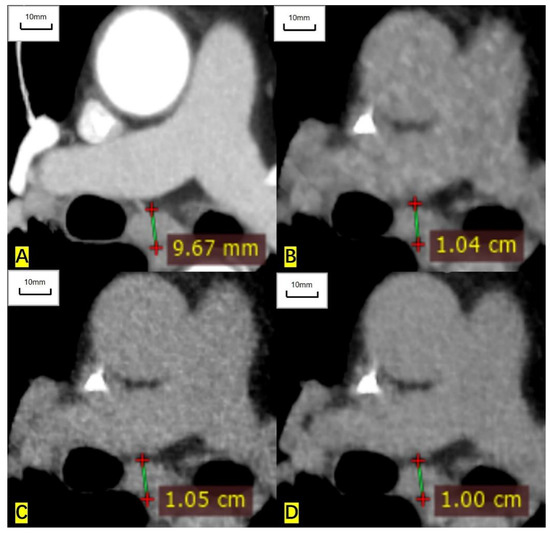

Figure 5.

A 65-year-old man had an enlarged subcarinal lymph node, and the histological result was unavailable. (A) The short diameter measured on the contrast-enhanced CT image is 9.67 mm. (B) The measured short diameter on the ASIR-V-80% reconstructed image is 10.4 mm. (C) The measured short diameter on the DLIR-M image is 10.5 mm. (D) The measured short diameter on the DLIR-H image is 10.00 mm. The short diameter is overestimated by 7.5%, 8.6%, and 3.4%, respectively, compared with that of contrast-enhanced CT.

For RECIST-defined nonmeasurable pulmonary target lesions, the correlation coefficient of measured diameter between ULDCT and contrast-enhanced CT was 0.977 (0.970 to 0.982), 0.987 (0.983 to 0.990), and 0.995 (0.994 to 0.996) for ASIR-V-80%, DLIR-M, and DLIR-H images, respectively. For mediastinal lymph nodes, the correlation coefficient was 0.937 (0.898 to 0.962), 0.939 (0.901 to 0.963), and 0.970 (0.951 to 0.982), respectively. For nonmeasurable hilar lymph nodes, the correlation coefficient was 0.994 (0.966 to 0.999), 0.969 (0.835 to 0.995), and 0.997 (0.982 to 0.999), respectively. The measured diameters of nonmeasurable target lesions in ULDCT were also highly correlated with those in contrast-enhanced CT (Table 4, Figure 4 and Figure 5).

For nonmeasurable pulmonary target lesions, Bland-Altman analysis showed a variation of 5.7% (4.7% to 6.7%), 5.1% (4.3% to 5.8%), and 2.2% (1.7% to 2.6%) for ASIR-V-80%, DLIR-M, and DLIR-H images against that in contrast-enhanced CT, respectively. For mediastinal lymph nodes, the variation was 6.1% (5.2% to 7.1%), 6.4% (5.4% to 7.4%), and 2.9% (2.2% to 3.5%), respectively. For hilar lymph nodes, the variation was 5.2% (4.3% to 6.1%), 6.4% (4.4% to 8.4%), and 3.2% (2.4% to 4.0%), respectively. Among the three reconstruction image sets, DLIR-H still showed the lowest variability (Table 5).